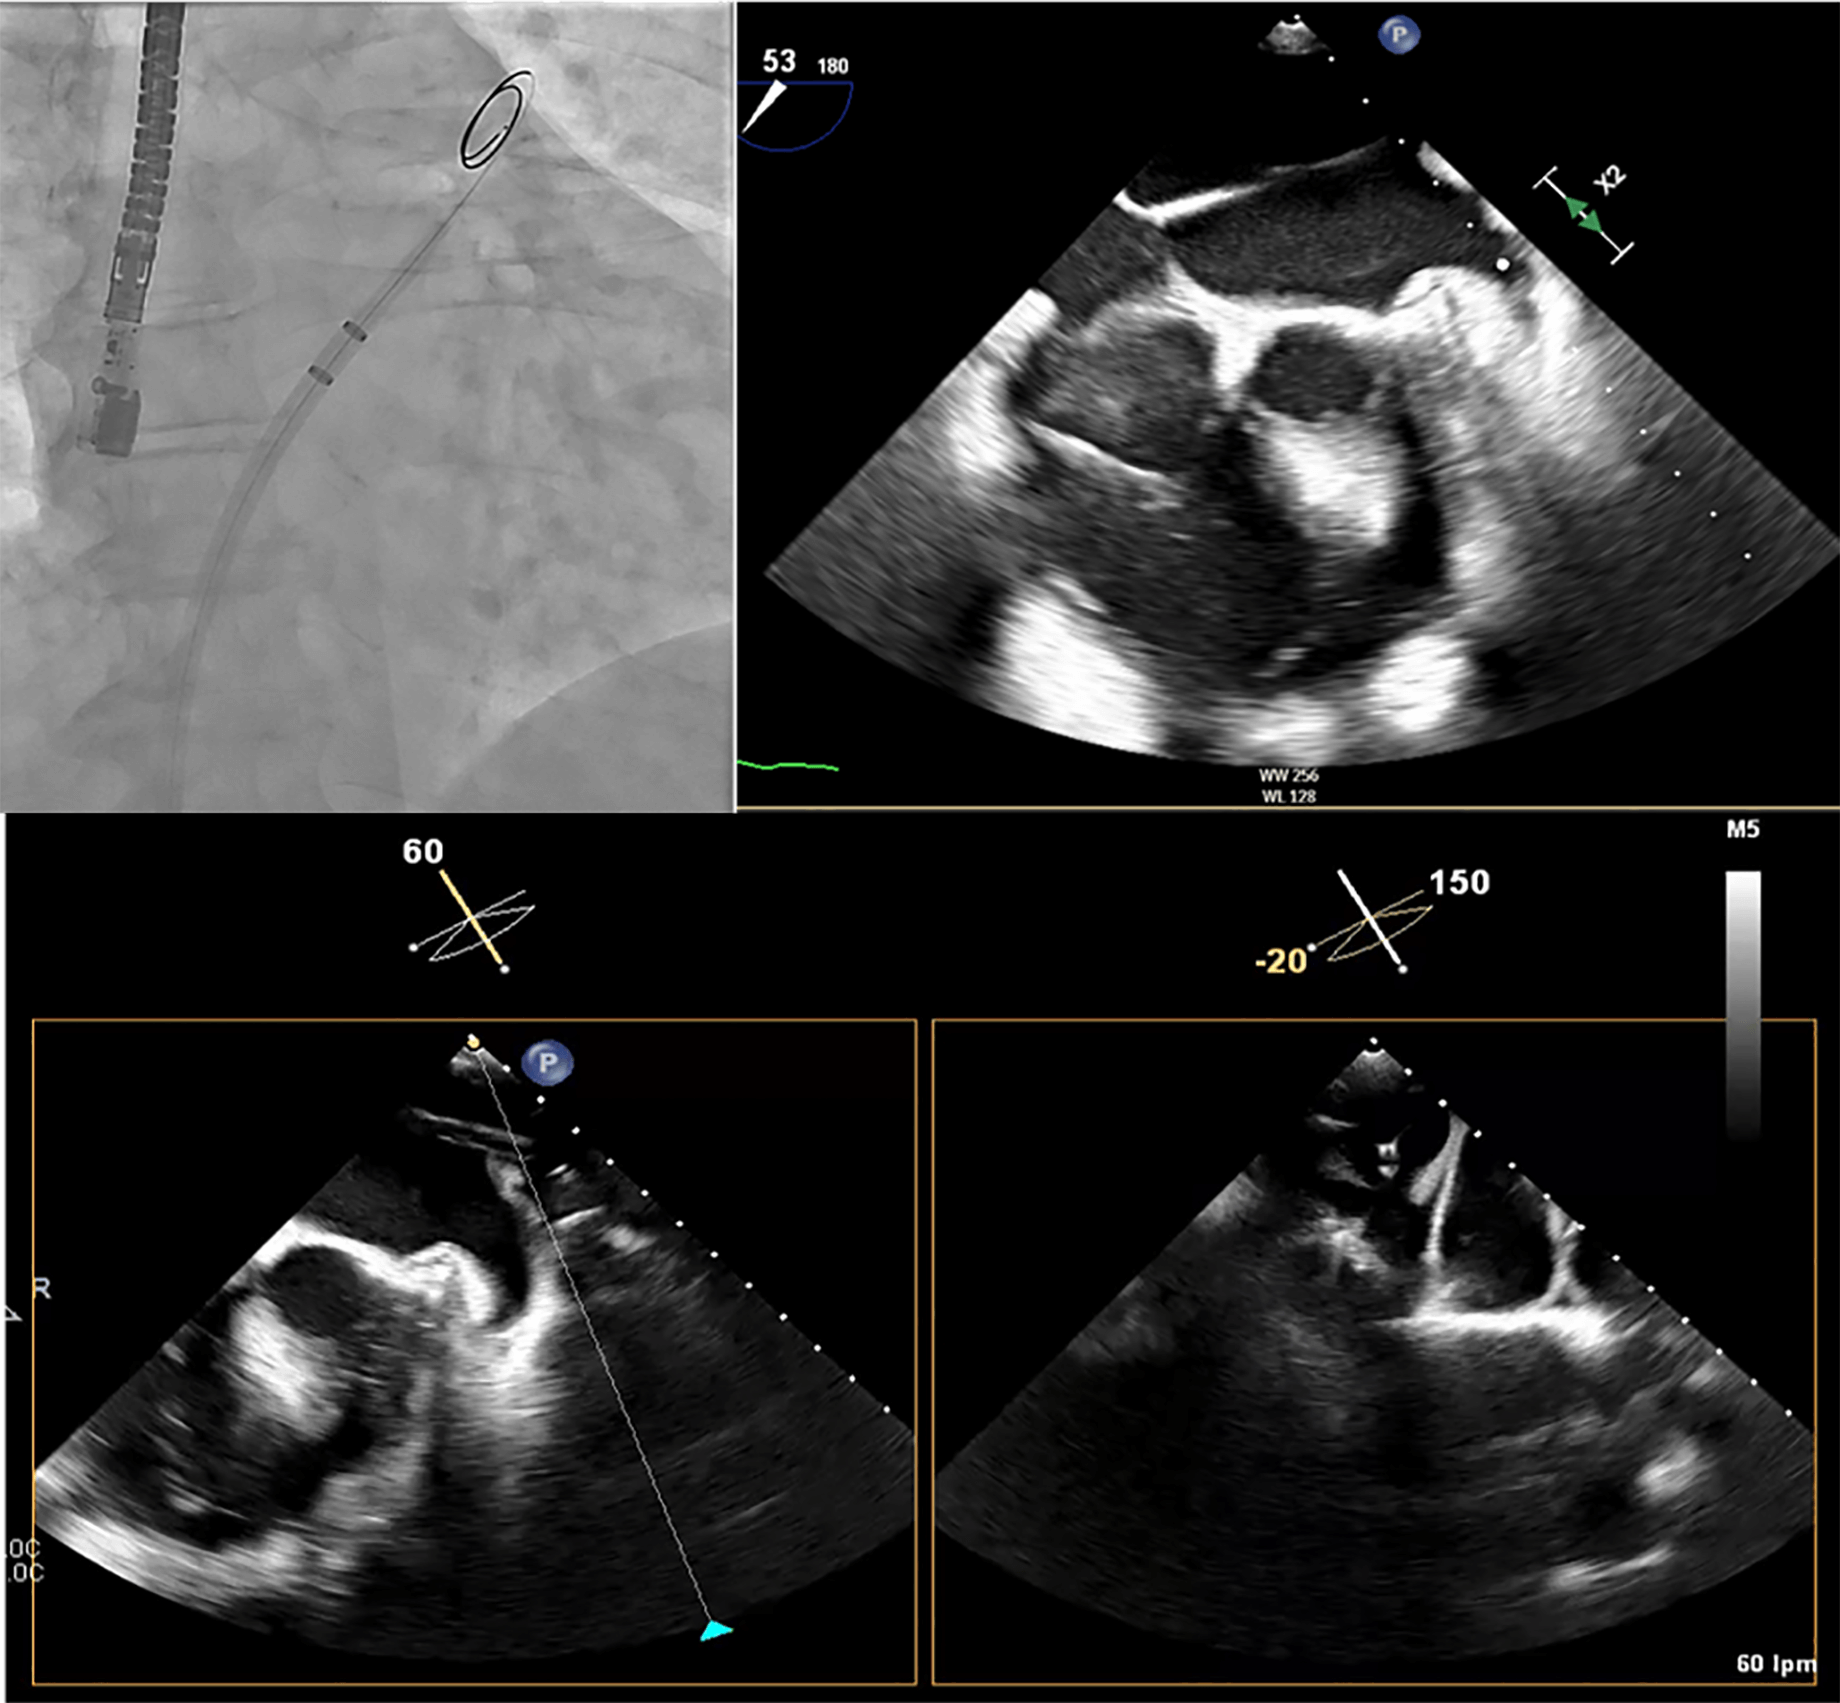

One of the most critical steps in LAAC is the TSP. The LAA is typically located in the anterosuperior portion of the LA and directed laterally and anteriorly. Consequently, an inferoposterior puncture within the fossa ovalis provides the most favorable trajectory for aligning the access sheath along the LAA’s long axis, thereby facilitating precise device positioning (Fig. 5) [15]. In cases where the LAA includes an additional, very anteriorly oriented lobe, a mid-fossa puncture—rather than an excessively posterior one—may provide better alignment with the target segment (Fig. 6). A TSP is traditionally performed using a Brockenbrough needle in combination with a transseptal sheath (Abbott, Abbott Park, IL, USA). We prefer the VersaCross® Transseptal System (Baylis Medical, part of Boston Scientific Corporation, Marlborough, MA, USA), which integrates a radiofrequency (RF) puncture system with an exchange-ready pigtail wire. This design facilitates both safe LA access and efficient navigation during the procedure. The pigtail wire, positioned within the transseptal sheath, is connected to an RF generator. Once the sheath tents the fossa ovalis appropriately, RF energy is applied, allowing the guidewire to cross into the LA, where it safely coils, thereby minimizing the risk of atrial wall injury (Fig. 7).

Fig. 6.

Middle and inferior transseptal puncture (TSP) approach. A transseptal puncture (TSP) in the inferior (A) and middle (B) portions of the fossa ovalis in a patient with an inverse chicken-wing morphology (C) of the left atrial appendage (LAA), clearly visualized in the angiographic image (D).